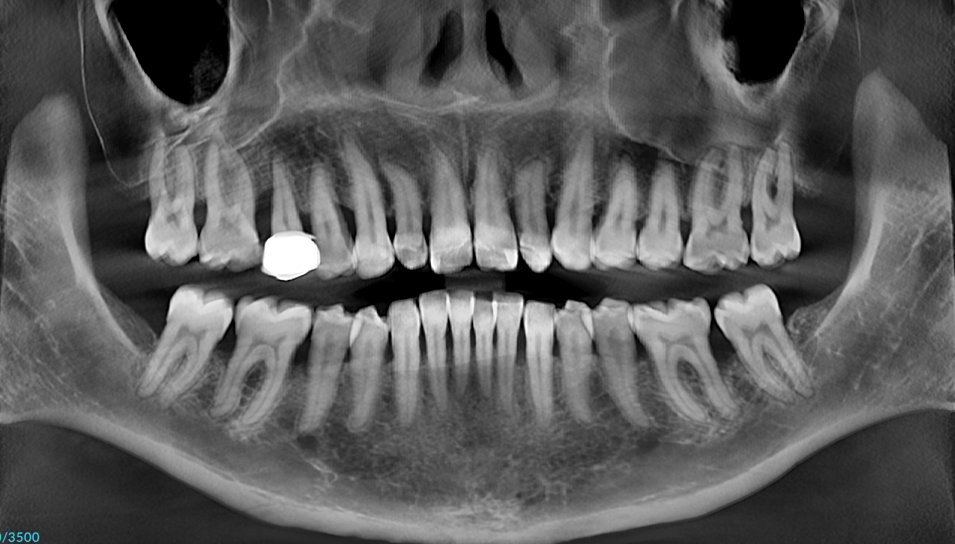

Your periodontal examination involves three key measurements. The current classification system, established by the 2018 World Workshop, categorizes disease by stage (I through IV for severity) and grade (A through C for progression speed).

- X-Rays (Radiographs): X-rays show the pattern and extent of bone loss. We can see whether bone has been lost evenly (horizontal loss) or whether craters and vertical defects have formed. This pattern directly determines which type of treatment you need.